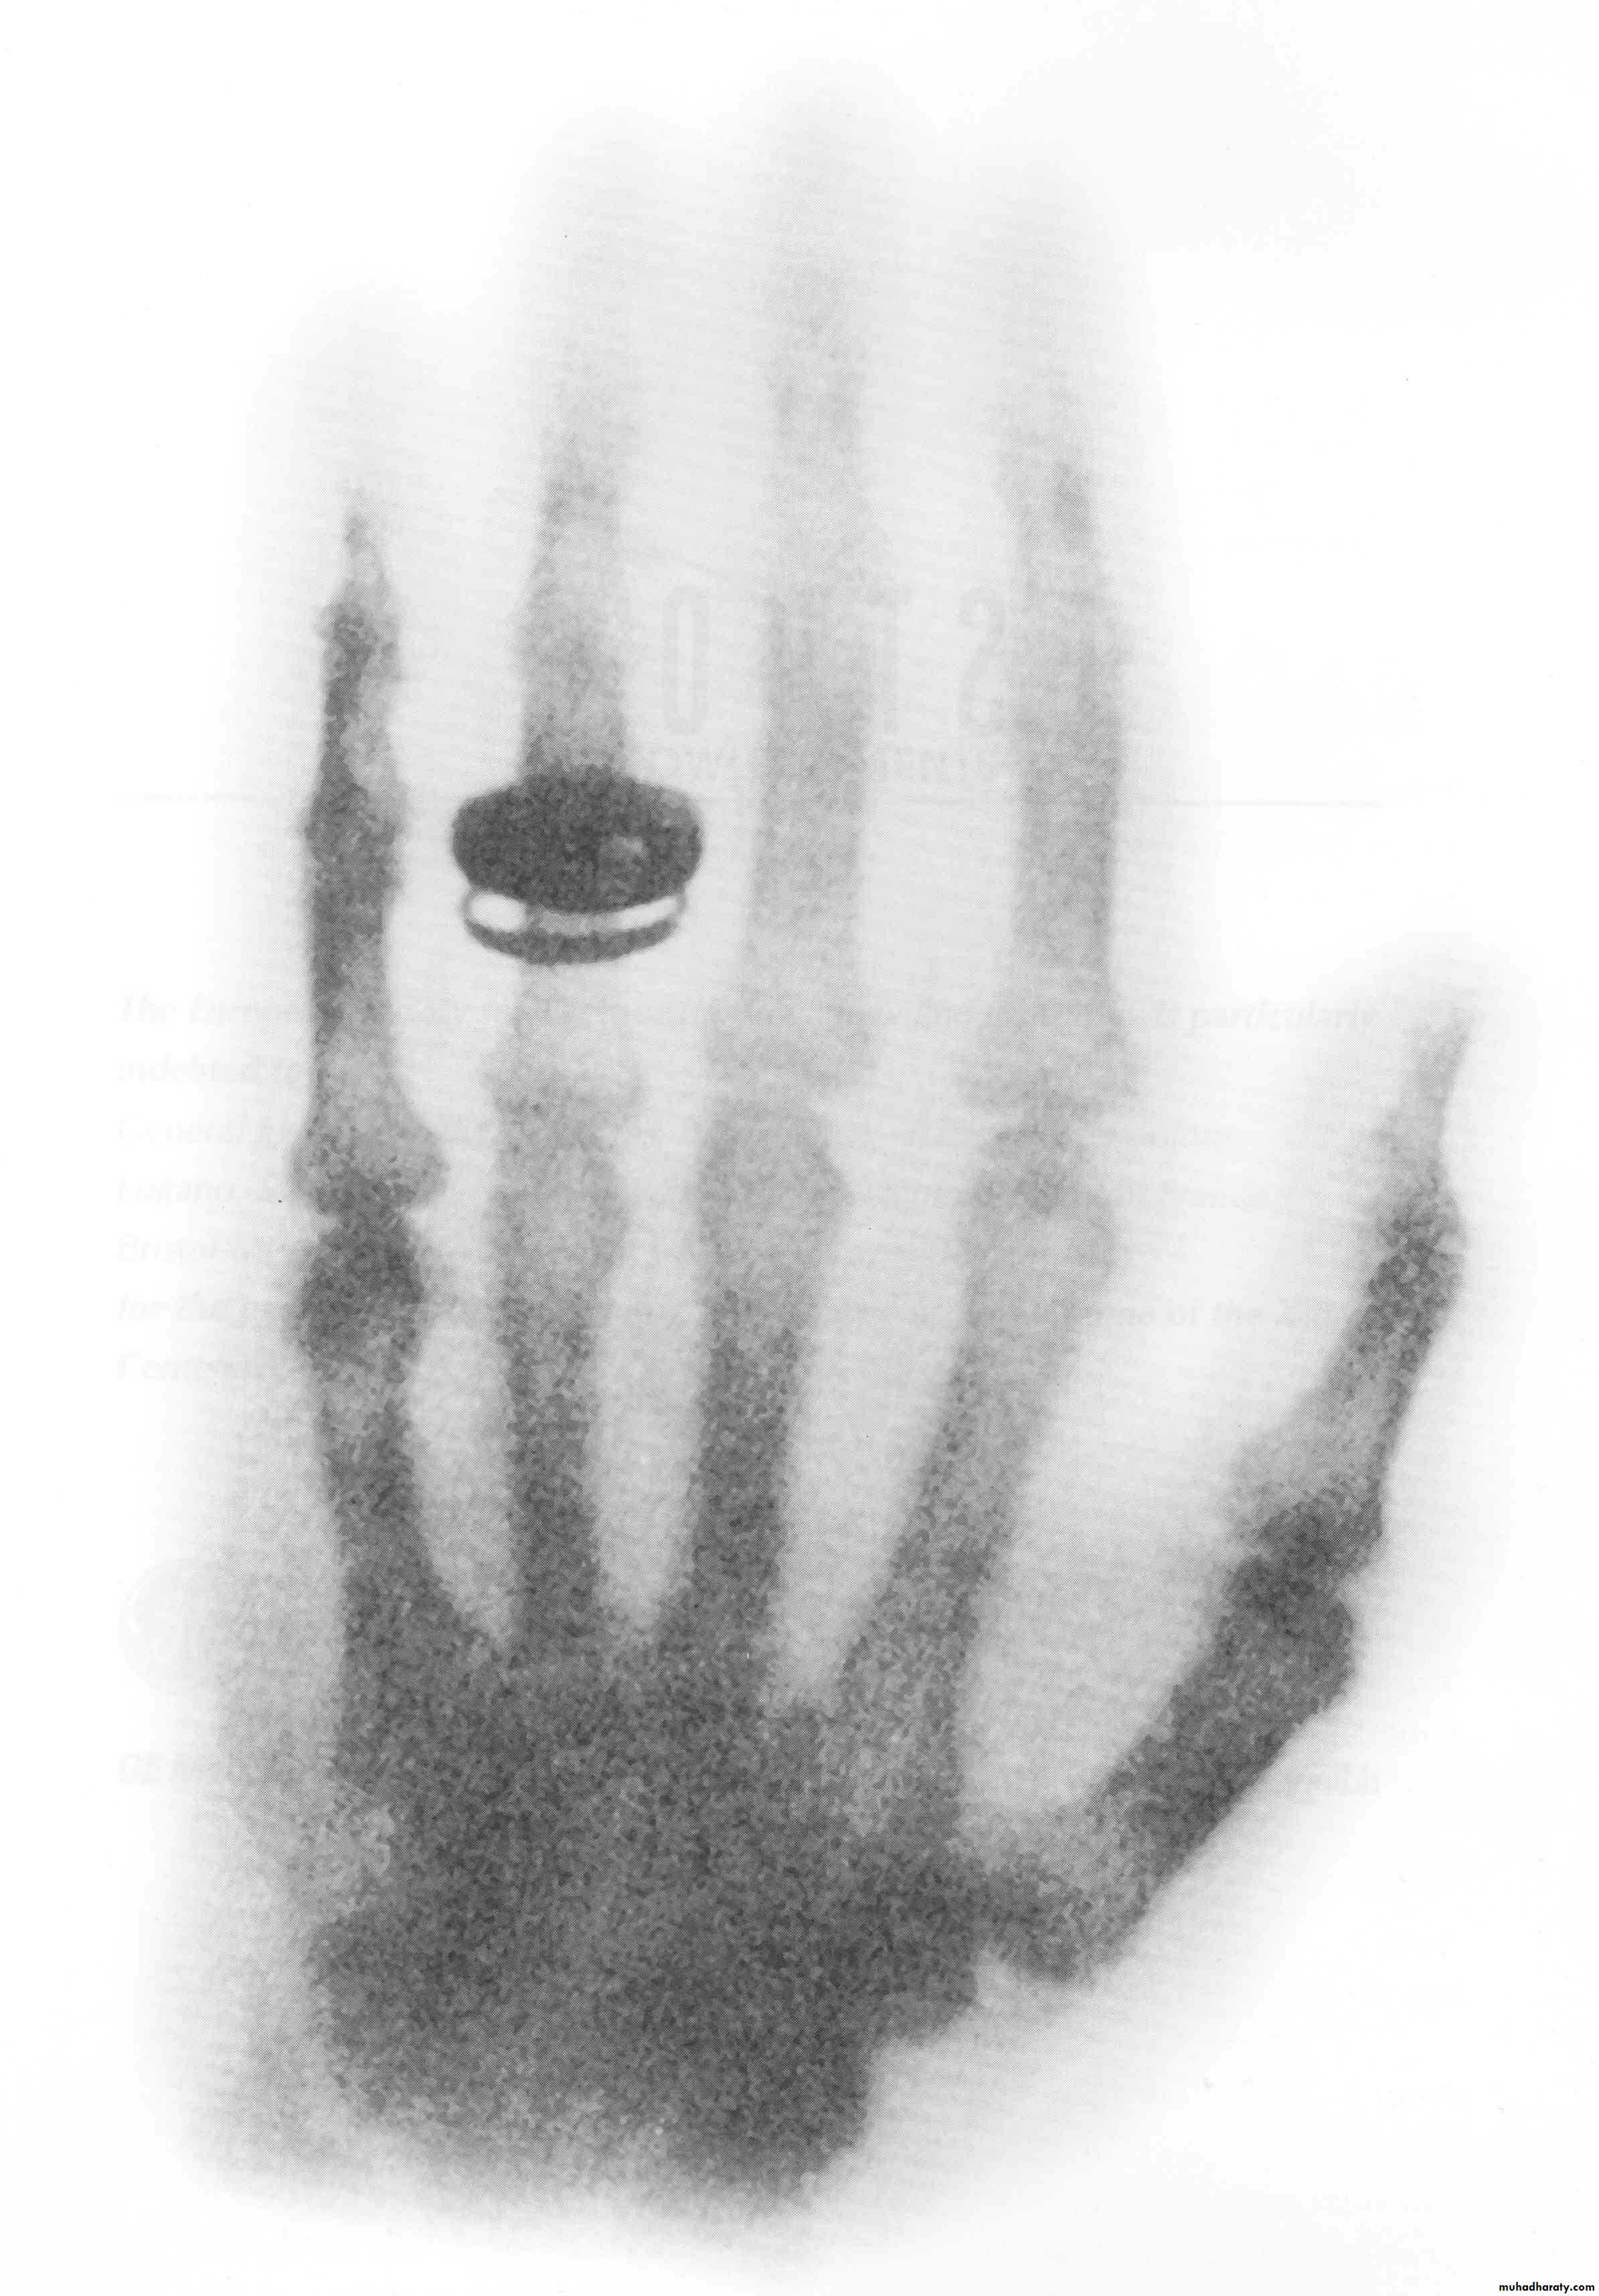

Radiograph of Frau Roentgen’s left hand